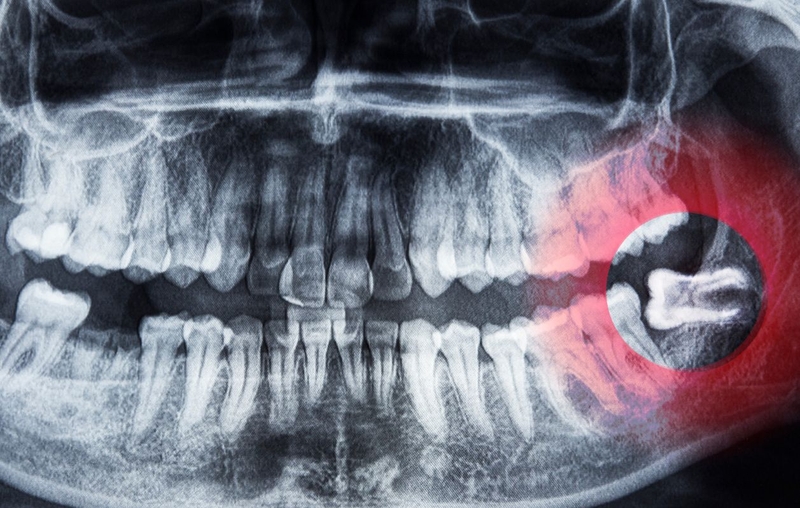

Sự phân bố răng khôn trong hàm răng có thể khác nhau giữa các cá nhân. Một số người có thể chỉ mọc từ một đến hai răng khôn, trong khi những người khác có thể mọc tất cả 4 răng khôn. Một số người có thể mọc răng khôn sớm hơn hoặc muộn hơn và thậm chí có người không bao giờ mọc răng khôn. Cấu trúc hàm răng cũng ảnh hưởng đến việc mọc răng khôn. Nếu hàm răng có đủ chỗ, răng khôn có thể mọc một cách suôn sẻ hơn. Ngược lại, nếu không đủ chỗ, răng khôn có thể gặp khó khăn trong quá trình mọc dẫn đến răng khôn mọc ngầm, răng khôn mọc lệch.

Với răng khôn mọc lệch, mọc ngầm, răng khôn bị sâu… gây đau đớn, ảnh hưởng đến sức khỏe răng miệng, việc nhổ răng khôn là phương pháp điều trị hiệu quả nhất. Trong trường hợp răng khôn mọc ngầm, có thể cần phẫu thuật để lấy răng khôn ra khỏi lớp nướu và xương hàm. Quyết định điều trị cho răng khôn sẽ được đưa ra sau khi bệnh nhân được kiểm tra bởi nha sĩ chuyên khoa để đảm bảo hiệu quả và an toàn.

Trước khi nhổ răng khôn, bác sĩ sẽ tiến hành kiểm tra và chụp X-quang để đánh giá vị trí và tình trạng của răng khôn. Thủ thuật nhổ răng khôn thường được thực hiện dưới tác động của gây tê cục bộ để giảm đau và khó chịu cho bệnh nhân. Trong một số trường hợp phức tạp, bác sĩ có thể sử dụng gây mê toàn thân. Sau khi nhổ răng, bác sĩ sẽ hướng dẫn bệnh nhân về cách chăm sóc và vệ sinh miệng để tránh nhiễm trùng và thúc đẩy quá trình lành vết thương.